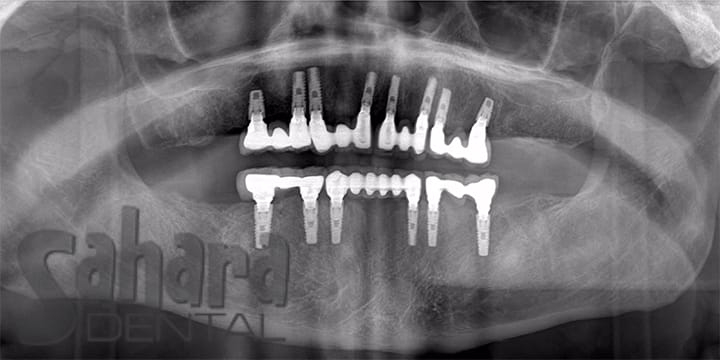

Full Mouth Implants for Restored Function and Smile

Complete implant placement and full mouth restoration expertly performed by Dr. Jamal in Hemet, California. This transformative treatment restored the patient’s natural bite, long-term stability, and confidence — delivering both function and a beautiful, natural-looking smile.